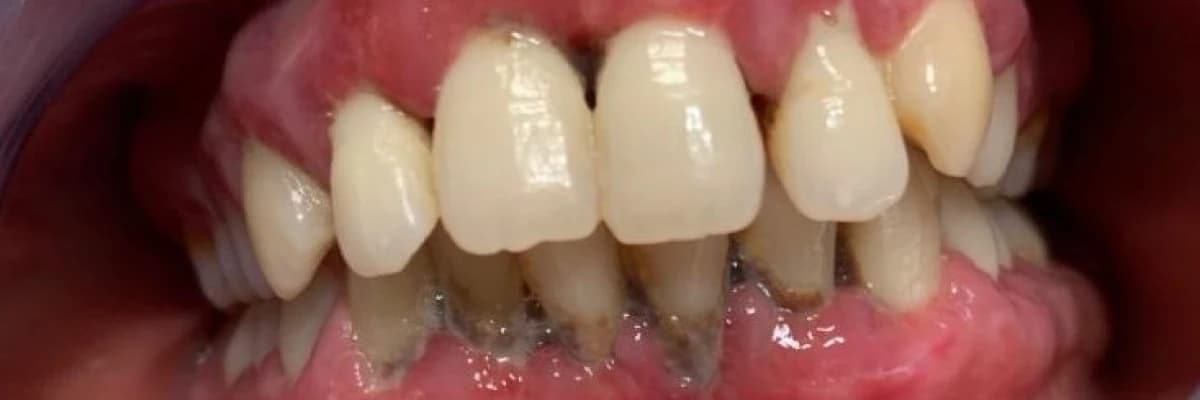

Periodontal hastalıklar ya da türkçeleştirilmiş şekli ile diş eti hastalıkları, diş köklerinin çevresindeki çene kemiğini eriterek dişetlerinin çekilmesi ve dişlerin sallanmasına (mobilite) neden olan çok ciddi bakteriyel enfeksiyonel hastalıklardır. Diş eti hastalıkları çok yaygındır. Yetişkinlerin %90'ında, çocukların %30'unda hastalığının çeşitli formları vardır. Toplumun %37'sinde şiddetli dişeti hastalığı görülmektedir. Çekilmek zorunda kalınan yetişkin dişlerinin %60'ında çekim nedeni çürük değil dişeti hastalığı olan periodontitistir.

Sağlıklı dişeti kanamaz. Periodontitis veya Gingivitis; Di şeti hastalıklarının en büyük belirtisi ise kanamadır. Çünkü bu rahatsızlıkların nerede ise tamamı ağrısız dolayısıyla da sinsidir. Dişeti kanaması alarm işareti olarak görülmeli ve bir an önce de Diş eti Hastalıkları ve Cerrahisi Uzmanı olan bir doktor tarafından muayene ve tedavi edilmelidir. Ve uygun aralıklarla ömür boyu uzman hekim kontrolünde kalınmalıdır. Geç kalındığında ağızdaki dişler sallanmaya başlar; Bunlar yapacak pek bir şey kalmadığının habercisidir. Tüm dişler kaybedilebilir. Dişeti kanamasının üzerinde duralım ve gerekeni yapalım: İŞ İŞTEN GEÇMEDEN!

Kanama, kızarıklık ve şişlik dişeti hastalığının çarpıcı belirtileridir. Dişeti hastalığında; çene kemiğinin erimesi sonucu dişlerin sallanmasına kadar geçen süreçte en rahatsız edici dolayısıyla da en dikkat çekici belirti kanamadır. Bu nedenle de dişeti kanaması çok ciddiye alınmalı ve görüldüğü anda takip edilerek doktora gidilmelidir.